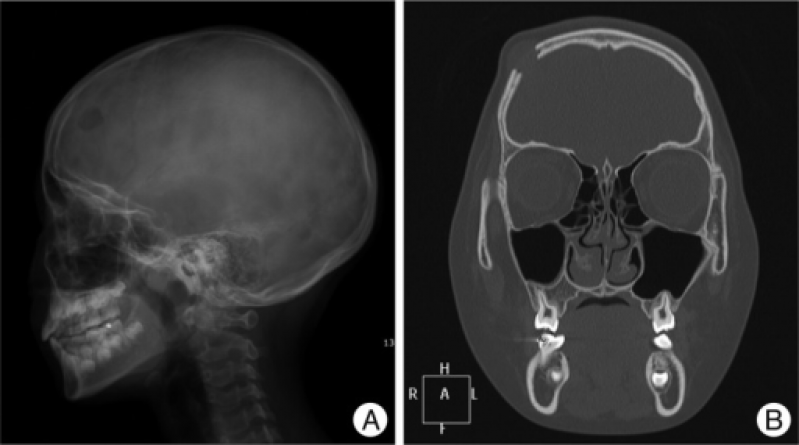

Exame de Imagem Tomografia do Crânio

Exame de Imagem Tomografia do Crânio

Exame de Imagem Tomografia do Crânio

Medicom ExamesUm exame de imagem é diferente dos exames endoscópicos, onde são inseridos tubos flexíveis com luz e lentes ou uma câmera de vídeo, dentro do corpo... Cotar Agora Saiba Mais